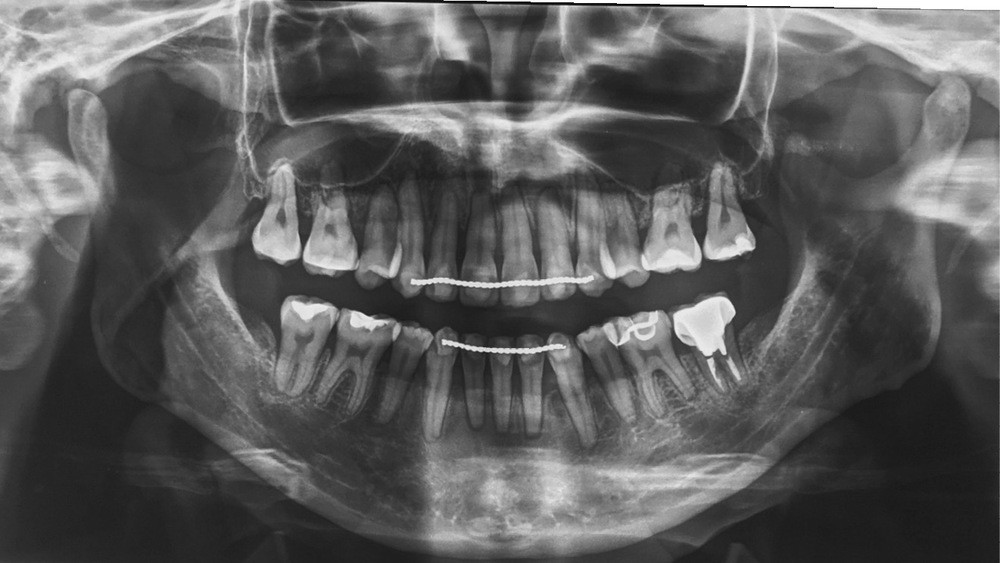

La patiente présente par ailleurs une parodontite chronique modérée stabilisée (Stade 3, grade C selon la classficaiton de Chicago 2018) et bénéficie d’une maintenance trimestrielle chez son parodontiste, qui nous donne son accord pour le traitement orthodontique moyennant un suivi très régulier.

Sur le plan dentaire, la patiente est en classe III droite et gauche, canine et molaire de 6 mm, avec une occlusion inversée antérieure localisée à 11, 12 et 22. Elle présente une dysharmonie dents-arcades sévère, une agénésie d’une incisive mandibulaire est à signaler, et les troisièmes molaires ont été extraites à l’âge de 21 ans.